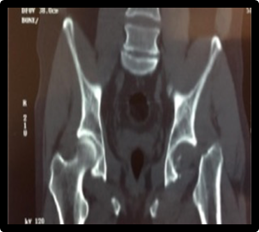

Presentamos el caso de un paciente de 49 años, trabajador de la construcción, sin patología previas, procedente del interior del Uruguay, quien otorgó su consentimiento verbal y escrito para la publicación de su caso. Sufre un accidente automovilístico en febrero del 2019, viajando como acompañante en asiento trasero sin cinturón de seguridad, sufriendo lesión de cadera izquierda al impactar la rodilla con el respaldo del asiento delantero. De la valoración inicial al momento de la asistencia en el lugar, no presenta lesión de cráneo, raquis, tórax ni abdomen y se constata miembro inferior derecho acortado, tumefacción en raíz de muslo y parestesias de miembro inferior derecho en territorio del nervio ciático poplíteo externo. Los pulsos distales estaban presentes y no presentaba otras lesiones del sistema músculo esquelético ni compromiso vascular. No se realizó ninguna maniobra sobre la cadera del paciente, ni en el lugar del accidente, ni en el centro asistencial. En la radiografía de frente, absolutamente atípica, se diagnostica luxación de cadera izquierda con fractura de cuello femoral, y el fragmento epifisario en dirección inversa (cuello hacia el acetábulo, y cabeza hacia el macizo trocantérico) (figura 1). La tomografía confirma luxación posterior del fragmento con la disposición antes mencionada, sin lesión ósea de la cabeza femoral, ni del acetábulo (figura 2, 3, 4, 5).

Figura 2: Tomografía corte coronal

Figura 3: Tomografía corte sagital

Figura 4: Tomografia Corte axial

Figura 5: Tomografía reconstrucción 3D

La estabilización inicial del paciente se realizó en un centro asistencial cercano al lugar del accidente, siendo derivado a un centro de tercer nivel con 12 horas de evolución. Se realiza una valoración imagenológica la cual confirma el diagnóstico (figura 1). La tomografía confirma la asociación lesional y descarta otras lesiones concomitantes. Antes del tratamiento definitivo no se utilizaron otros métodos diagnósticos para descartar lesiones vasculares o confirmar la lesión neurológica del paciente. Dada la edad del paciente, el tiempo de evolución, el desplazamiento de la lesión ósea asociada a la luxación con alta probabilidad de osteonecrosis, se decidió realizar una artroplastia total de cadera. La cirugía se llevó a cabo 16 días luego del accidente. Por vía anteolateral trans-glúteo medio, al abrir la fascia, la cabeza femoral estaba subcutánea en el sector posterolateral (figura 6). Se buscó el nervio ciático que estaba sano. Se utilizó una prótesis cementada, con tallo cónico pulido, con cabeza 28 Metal-Polietileno.